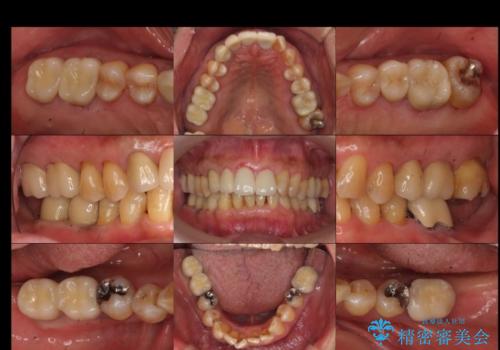

奥歯が割れてしまった インプラントでかめるように 全体的な治療も

ブリッジにできない位置であったため、インプラントでかめるようにしました。

また、向かい合う上の歯が挺出(伸び出してしまうこと)しており、インプラントを入れることが難しかったため、長さを短くかぶせ治しました。

- 約250万円 右下67 インプラント2本(ストローマンインプラント20万円、カスタムアバットメント10万円、シリンダーTeC 2万円 以上2本、マイナーGBR5万円) 再根管治療 (前歯 9万円x1、小臼歯11万円x1 大臼歯:専門医による再治療 15万円x3本) ジルコニアクラウン(右上2367、右下I6I7、左上56 10万円x8 )仮歯 1万円x8本 ファイバーコア 2万円x5 セラミックインレー(左上5) 7万円x1 フラットタイプナイトガード 3万円費用は治療当時の料金となります

セラミックが欠けるのを防ぐため、また、左上7は対合歯がなく挺出してしまうのを防ぐため、ナイトガードを就寝時に装着していただいています。